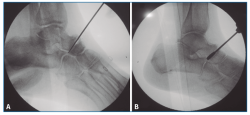

No se pudo realizar una valoración completa del resultado de la corrección clínica por no disponer de fotografías pre- y postoperatorias de todos los pacientes (Figura 5), aunque, como hemos comentado anteriormente, se valoró la evolución radiológica en la totalidad de los pacientes (Figura 6).

Figura 5. Aspecto clínico pre- (A y C) y postoperatorio (B y D) mostrando la corrección del valgo del pie izquierdo, así como la convexidad de la cara medial y el hundimiento del arco interno.